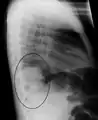

Normal AP CXR

AP CXR showing left lower lobe pneumonia associated with a small left sided pleural effusion

AP CXR showing right lower lobe pneumonia

AP CXR showing pneumonia of the lingula of the left lung

Right upper lobe pneumonia as marked by the circle.

Left upper lobe pneumonia with a small pleural effusion.

Right lower lobe pneumonia as seen on a lateral CXR